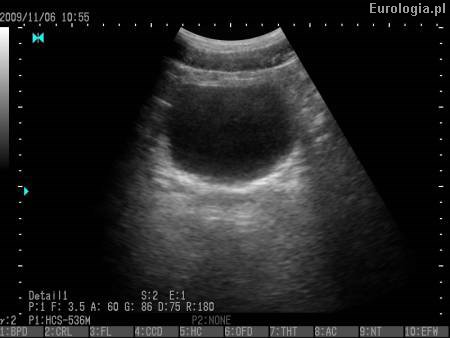

Zaleganie moczu po mikcji - PVR określa się za pomocą ultrasonografii. Po oddaniu moczu lekarz badaniem USG oceni czy w pęcherzu pozostaje mocz. W zależności od wyniku zaproponuje Panu dalsze leczenie.

Fot. Pęcherz moczowy - obraz USG.

Więcej informacji na temat ultrasonografii w diagnostyce układu moczowego można znaleźć w dziale: USG układu moczowego. Ocena zalegania moczu przy użyciu cewnika jest metodą historyczną.